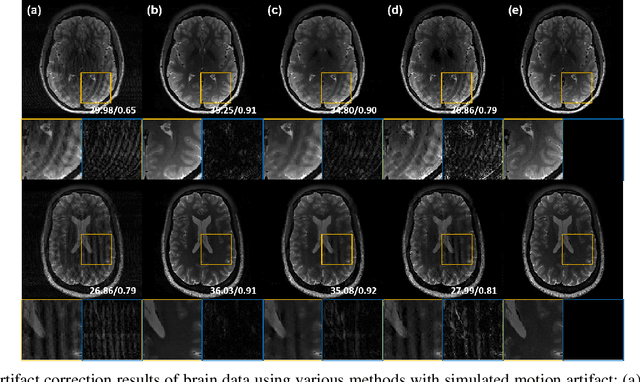

Recently, deep learning approaches for MR motion artifact correction have been extensively studied. Although these approaches have shown high performance and reduced computational complexity compared to classical methods, most of them require supervised training using paired artifact-free and artifact-corrupted images, which may prohibit its use in many important clinical applications. For example, transient severe motion (TSM) due to acute transient dyspnea in Gd-EOB-DTPA-enhanced MR is difficult to control and model for paired data generation. To address this issue, here we propose a novel unsupervised deep learning scheme through outlier-rejecting bootstrap subsampling and aggregation. This is inspired by the observation that motions usually cause sparse k-space outliers in the phase encoding direction, so k-space subsampling along the phase encoding direction can remove some outliers and the aggregation step can further improve the results from the reconstruction network. Our method does not require any paired data because the training step only requires artifact-free images. Furthermore, to address the smoothing from potential bias to the artifact-free images, the network is trained in an unsupervised manner using optimal transport driven cycleGAN. We verify that our method can be applied for artifact correction from simulated motion as well as real motion from TSM successfully, outperforming existing state-of-the-art deep learning methods.